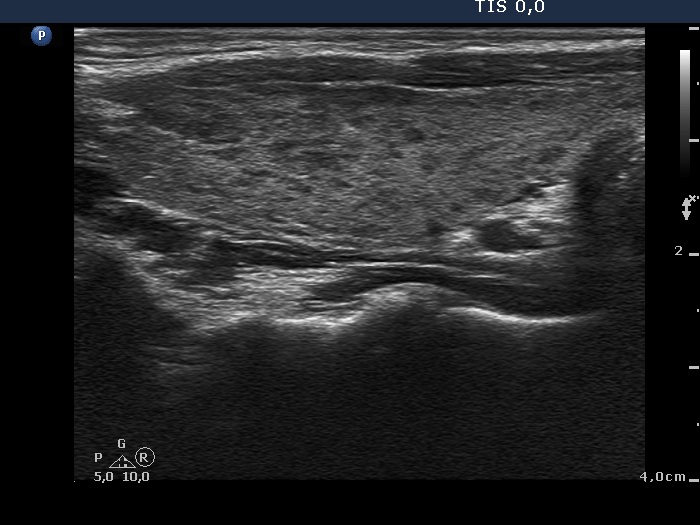

First examination (first and second rows of images):

Clinical presentation: A 33-year-old woman was referred for an evaluation of complaints suggesting hyperthyroidism. The patient was never pregnant.

Palpation: no abnormality.

Results of blood test: TSH undetectable, FT4 31.0 pM/L, aTPO 703 U/mL, TSAb 0.5 U/L (normal value < 1.5).

Ultrasonography: A diffusely hypoechogenic thyroid was found with several discrete lesions. The vascularization was increased.

Cytology was performed from the right lobe.Cytological diagnosis: benign pattern corresponding to hyperthyroidism without any signs of thyroiditis.

Considering the results of investigation, low dose (daily 15 mg) methimazole was administered.